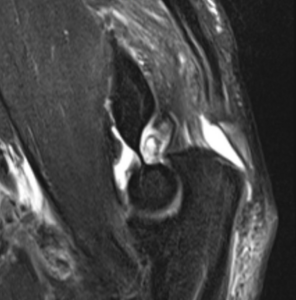

MRI

– Gold standard for confirming diagnosis; Differentiates partial from complete tears; Identifies associated ligamentous injuries; Helps classify injury severity and guide treatment decisions; May overestimate tear severity compared to surgical findings